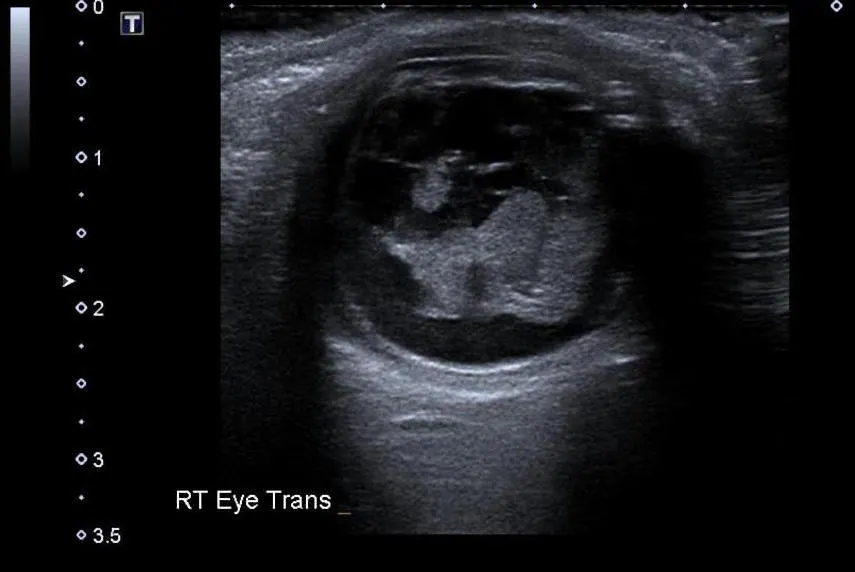

Lens Detachment

Presentation: May present as decreased vision with a normal pupillary response and without signs of open globe injury

Note: Usually due to trauma. Occurrences in children or secondary to minor trauma should prompt investigation for an underlying genetic cause

Findings: Posteriorly-displaced lens

Sensitivity 84.6%, Specificity 98.3%, Positive Likelihood Ratio 49.5, Negative Likelihood Ratio 0.15 (Haghighi 2014, PMID: 26495362)